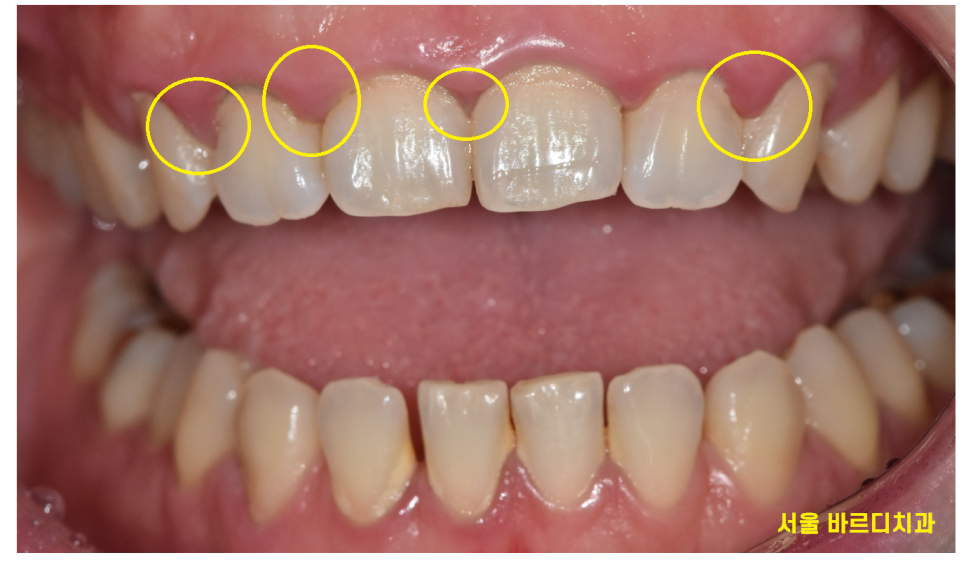

241001 입덧이 심해 양치를 못하고 잇몸이 많이 부은 환자분